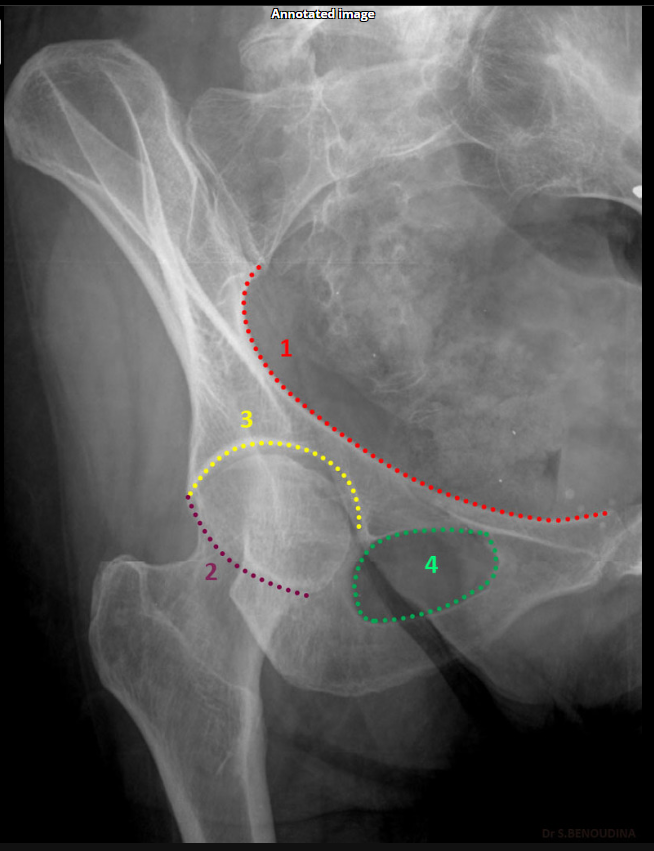

Which acetabular rim does the internal oblique Judet view show?

Posterior rim. (SHOWN #2 PURPLE)

<p>Posterior rim. (SHOWN #2 PURPLE)</p>

Anterior column. (SHOWN #1 RED)

<p>Anterior column. (SHOWN #1 RED)</p>

Which acetabular rim does the external oblique Judet view show?

Anterior rim. (SHOWN #2 GREEN)

<p>Anterior rim. (SHOWN #2 GREEN)</p>

Which acetabular column does the external oblique Judet view show?

Posterior column.ilioschial(SHOWN #1 ORANGE)

<p>Posterior column.ilioschial(SHOWN #1 ORANGE)</p>

What does the iliopubic line represent in Judet views?

Anterior column.(SHOWN #1 RED)

<p>Anterior column.(SHOWN #1 RED)</p>

What does the ilioischial line represent in Judet views?

Posterior column.(SHOWN #1, ORANGE)

<p>Posterior column.(SHOWN #1, ORANGE)</p>